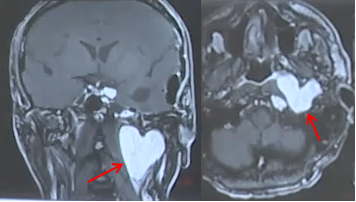

我的脑子里有颗爱心?这是肿瘤危险“示爱”

眼前这个这颗形状酷似爱心的颅底肿瘤,“爱”得令人窒息!请停止继续发散你的“爱”。

这个肿瘤长得乱七八糟、张牙舞爪、无孔不入,实在太猖狂了!有的脑瘤可以不开颅从鼻子进去就取出,可是这个瘤子,从海绵窦一路蔓延至颈部,像一团盘踞的荆棘,一个入路无法解决。

更棘手的是,患者此前已在其他医院接受过一次手术——然而,那次手术仅仅将肿瘤“一分为二”。上方的海绵窦部分,下方的颈静脉孔部分。